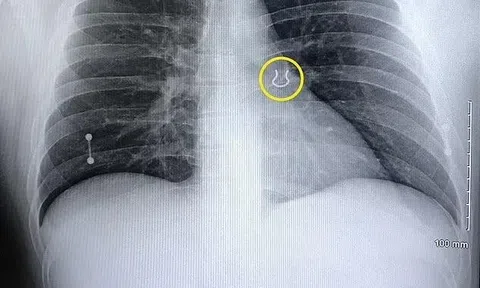

Người đàn ông nhập viện vì ho dữ dội, ảnh chụp X-quang tiết lộ điều khó tin

Các bác sĩ lo ngại người đàn ông bị viêm phổi nhưng kết quả chụp X-quang lại cho thấy điều bất ngờ.